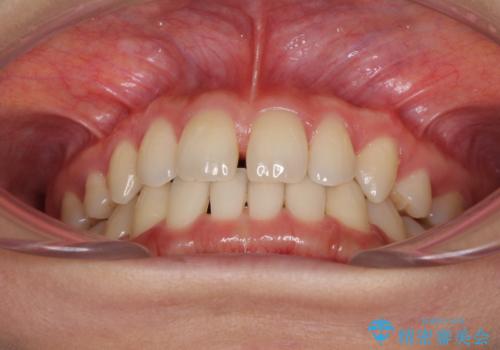

- 以前の矯正治療の後戻りにより、上の前歯にスペースができたことを気にして来院された患者様です。

インビザラインを用いて前歯のスペースを閉じつつ、上下の咬み合わせを構築していくこととしました。

隙間の空いてしまった前歯は、矯正治療で治療を行っても後戻りが起こりやすい傾向にあります。

マウスピースの保定装置をしっかりと装着しても空いてしまうため、細いワイヤーによる保定を併用することで後戻りを防止しています。